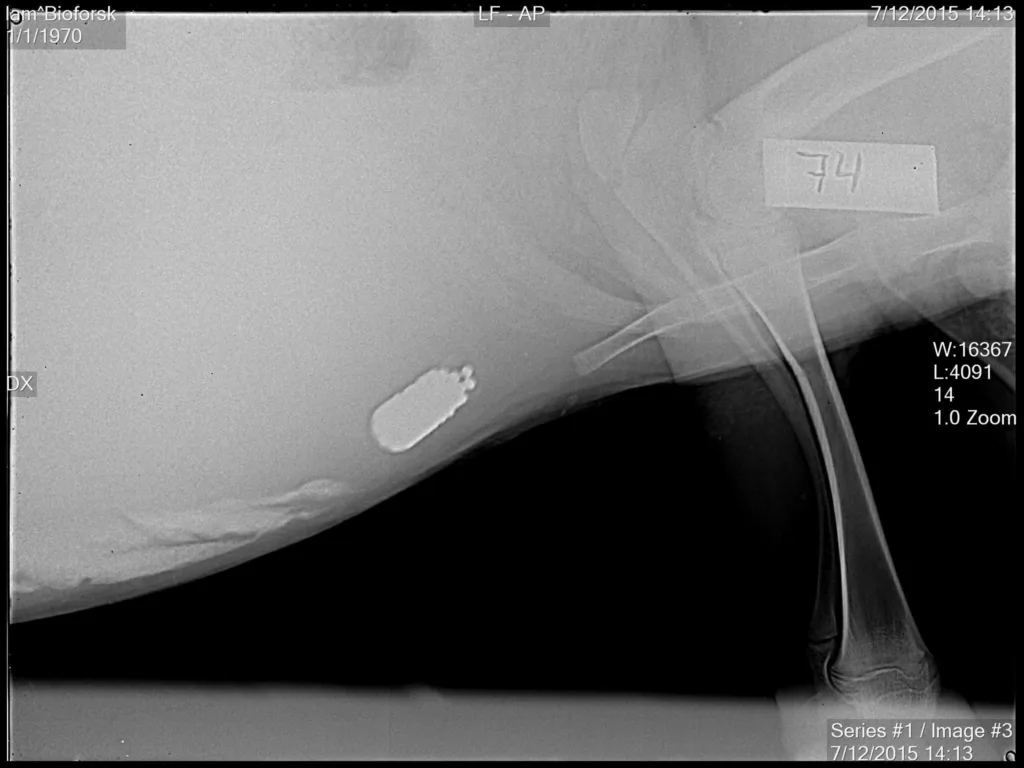

Kapselen er testa i tre ulike størrelser, fra tre til fire centimeter lengde og med vekt fra 8 til 18 gram. Kapselene ble produsert ved Universitetet i Oslo, og testa på 6 lam på ca 2 mnd (vekt 16-22 kg). Kapslene var lett å gi med et standard instrument som brukes til å gi parasittmiddel.

-Vekt og størrelse på kapslene var hensiktsmessige og kan legges til grunn for videre arbeid, sier forsker Marianne Lilletvedt Tovsen ved Universitetet i Oslo. Hun og Krister Gjestvang Grønlien har hatt ansvaret for utforming og produksjon av de nye kapslene.

- Røntgenfotografering av lammene viste at alle kapslene lå fint plassert i nettmagen etter at de var lagt inn, fortsetter hun.

-Kapslene lå i nettmagen i omtrent fire uker, noe vi mener er tilstrekkelig til å være virksomme i den kritiske perioden for utvikling av alveld på utmarksbeite. Kapslene gjorde ikke skade på fordøyelseskanalen. Lam som fikk lagt inn kapsler la på seg og vokste like fort som andre lam, sier veterinær og forsker Kristin Sørheim ved NORSØK. Hun hadde ansvar for testing av kapslene på lam.